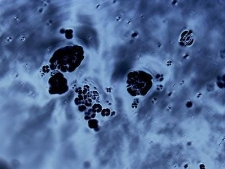

Zdjęcie wykonano przy użyciu mikroskopu polaryzacyjnego. Przedstawia sferulity otrzymane z insuliny z trzustki bawolej ; Praca nadesłana na 3nd Microscopic Art Non-Limited International Annual Contest MANIAC 2021 ; click here to follow the link